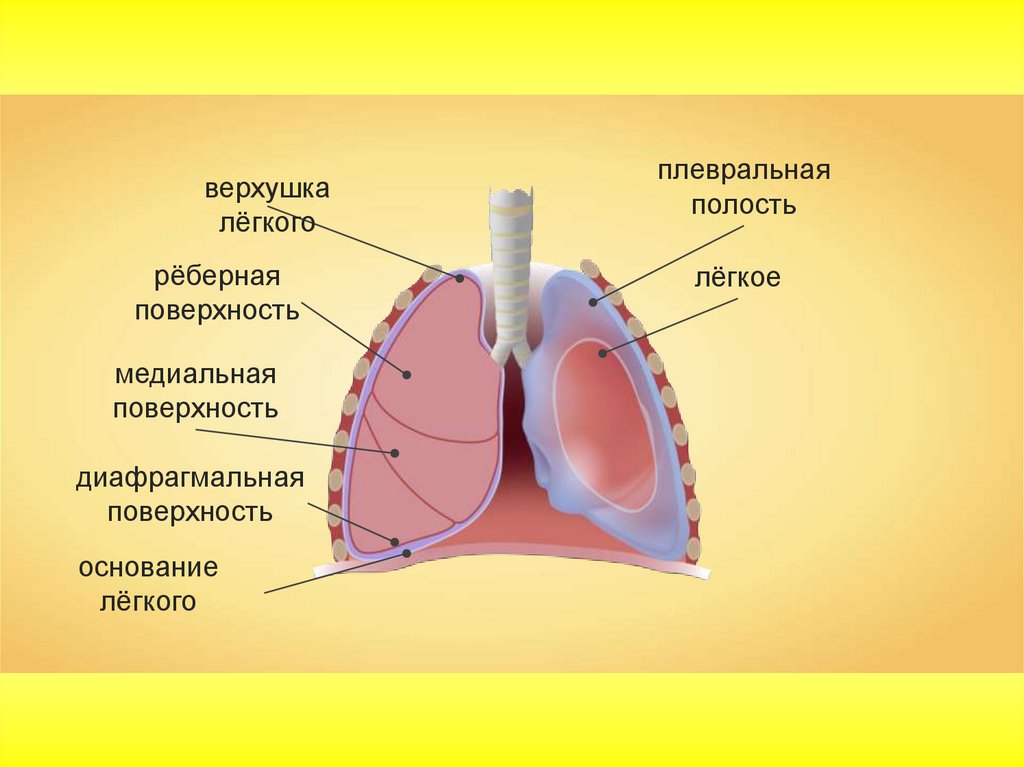

Анатомия межплеврального пространства